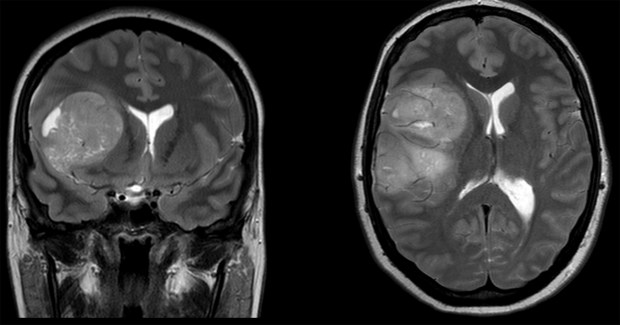

Tumores do Sistema Nervoso Central

Tumores dos Sistema Nervoso Central englobam tumores no cérebro, tronco cerebral, cerebelo e medula espinhal.

Se você recebeu o diagnóstico ou uma suspeita de um tumor cerebral, saiba que a lista de tipos de tumores é gigante. Muitos são passíveis de tratamento e para alguns tipos há excelentes chances de cura. No entanto, alguns são malignos, embora passíveis de tratamento. Continue lendo “Tumores do Sistema Nervoso Central”